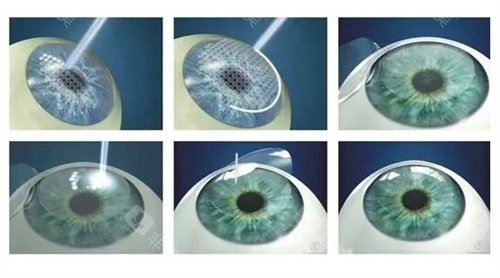

作为国内外规模比较靠前的眼科连锁机构,爱尔眼科在角膜交联领域优先实现三大技术升级:

免核黄素浸泡步骤,手术时长缩短至10分钟

采用370nm比较准紫外线,对角膜内皮零损伤

飞秒激光辅助移植吻合精度达0.01毫米